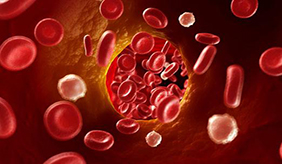

造血干细(xì)胞移(yí)植(HSCT)是将健(jiàn)康(kāng)的(de)造(zào)血干细胞输注给放、化疗后的患者,以替代患(huàn)者病态(tài)或衰竭(jié)的骨(gǔ)髓,使患者(zhě)造血和......